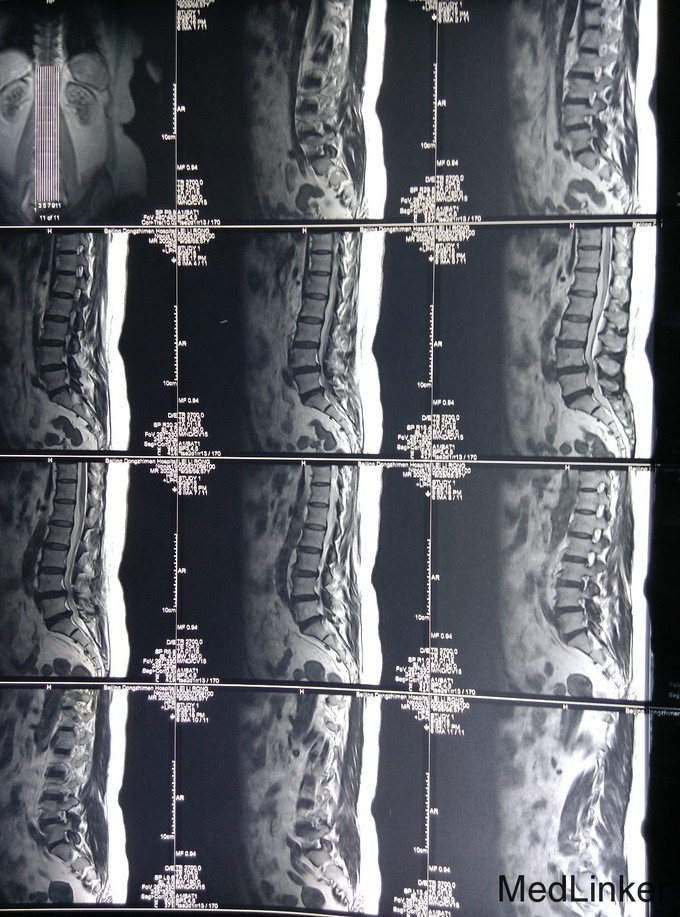

查体:脊柱生理弯曲存在,无腰椎侧突畸形,腰4-骶1椎旁压痛和深部扣击痛(+),腰部活动稍受限,直腿抬高试验双侧阴性,双下肢浅感觉无明显减退,双下肢肌力4级,双下肢膝反射和踝反射稍减弱,髌阵挛、踝阵挛未引出。病理反射未引出,肛周浅感觉正常,肛门反射正常。 腰椎CT及腰椎MRI示:L4-5、L5-S1椎间盘突出,椎管狭窄,黄韧带肥厚,相应硬膜囊受压。

诊断:腰椎管狭窄症、腰椎间盘突出、腰椎骨关节病 治疗:入院后完善相关检查,无明显手术禁忌症,于手术室全麻下行腰4-5、腰5-骶1椎板切除、椎管减压、椎弓根内固定术,